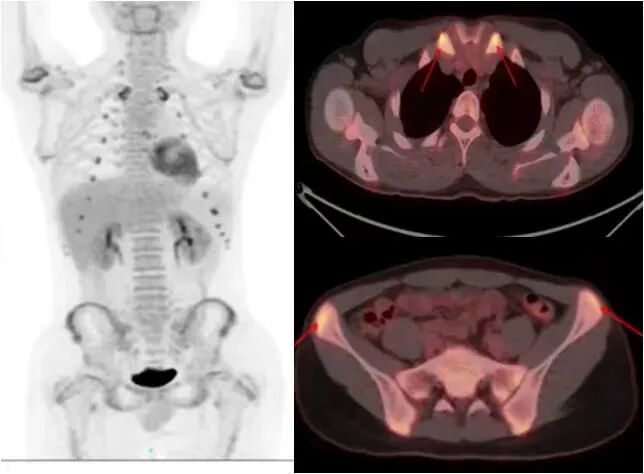

图片

胃癌全身广泛转移

女性,37岁,左乳癌术后转移再分期。

显示纵隔、双肺门、左上胸壁转移灶部位多个异常代谢明显增高区。

观察疗效